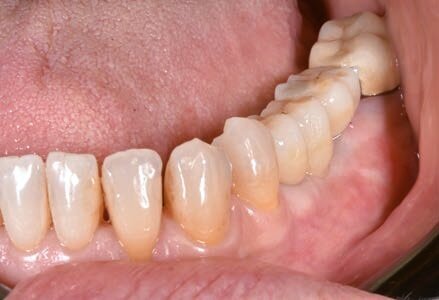

Dopo 6 mesi abbiamo effettuato delle Rx di controllo e misurato nuovamente il valore ISQ. Dopo aver riscontrato valori positivi abbiamo svitato le viti di guarigione e abbiamo avvitato gli specifici REXmarkers direttamente sugli impianti REX PiezoImplant. Abbiamo quindi effettuato un’impronta digitale con l’ausilio di uno scanner digitale Carestream 3600. Con l’esportazione dei file STL è stato possibile realizzare una protesi avvitata disegnata con Exocad*** che dispone al suo interno delle librerie protesiche REX PiezoImplant. È stato quindi consegnato il manufatto protesico definitivo che è stato avvitato a 25 N dopo aver controllato radiograficamente il corretto accoppiamento.

Fig. 18 - Visione vestibolare del manufatto protesico e della rigenerazione vestibolare fatta a fini estetici.